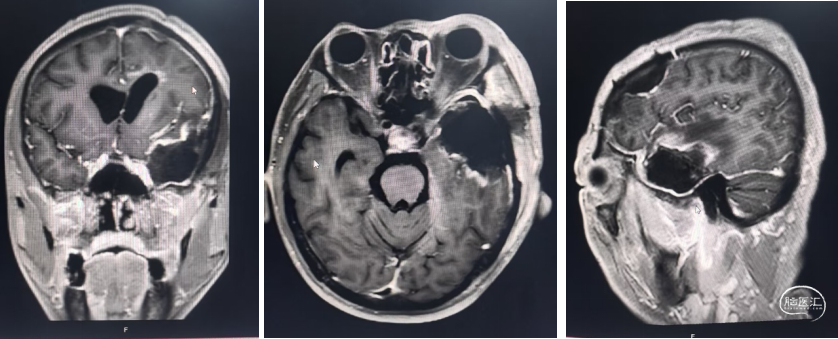

右侧桥小脑角区脑膜瘤切除术:

患者信息:患者女,69岁,因头部不适到医院就诊,在院做MRI检查,影像结果显示:右侧桥小脑角区可见一大小约30.1mm x 18.5mm x 24.9mm的不规则团块影,呈T1等/低信号T2等信号,T2FIair呈低/稍高信号,DWI呈等/稍高信号,轮廓较清晰,临近右侧小脑半球受压。

患者信息:患者男,52岁,既往行 左侧额叶肿瘤切除术+颅骨修补术,近日头部不适,到医院就诊,在院做MRI检查,影像结果显示:左侧颞叶见不规则等/稍长T1、稍长/长T2信号,DWI呈高/等信号,ADC呈高/低混杂信号,周围见片状长T2水肿信号,范围约25.8mmX20.5mmX17.6mm增强呈花环状强化。

患者信息:患者女,69岁,因头部不适到医院就诊,在院做MRI检查,影像结果显示:右侧桥小脑角区可见一大小约30.1mm x 18.5mm x 24.9mm的不规则团块影,呈T1等/低信号T2等信号,T2FIair呈低/稍高信号,DWI呈等/稍高信号,轮廓较清晰,临近右侧小脑半球受压。

患者信息:患者男,52岁,既往行 左侧额叶肿瘤切除术+颅骨修补术,近日头部不适,到医院就诊,在院做MRI检查,影像结果显示:左侧颞叶见不规则等/稍长T1、稍长/长T2信号,DWI呈高/等信号,ADC呈高/低混杂信号,周围见片状长T2水肿信号,范围约25.8mmX20.5mmX17.6mm增强呈花环状强化。